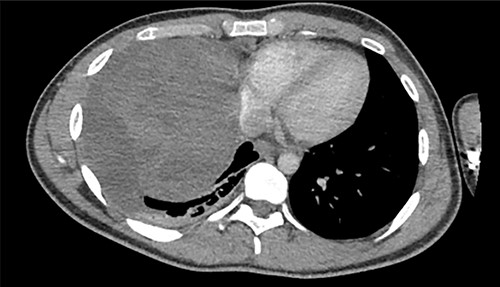

A 22-year-old male patient with no significant medical or surgical history and no smoking history presented to the emergency department for evaluation of persistent cough for 3 weeks. The cough was initially associated with chest pain, which then subsided. He denied fever, chills, nasal congestion, shortness of breath and sore throat. A viral panel including COVID-19 was negative and patient was vaccinated against COVID-19. Chest X-ray (Fig. 1) demonstrated a large right pleural effusion with right lower lung consolidation. To further investigate the chest X-ray findings, a computed tomography (CT) of the thorax (Fig. 2) was performed, revealing a 17.2 cm mass occupying the right hemithorax causing a leftward mediastinal shift and narrowing of the right-sided bronchi. To better determine the etiology of the mass, a biopsy was obtained via CT-guided fine needle aspiration. Although analysis of this specimen exhibited mostly necrotic material, it also showed nests of monomorphic epithelial-like cells with many small mature lymphocytes and findings consistent with a thymic neoplasm. Germ cell tumor markers were negative. The beta-hCG, AFP and LDH markers were also negative. However, a more definitive diagnosis was unable to be determined due to the scant amount of collected specimen. Given the clinical, radiographic and pathologic findings, the patient was scheduled for resection of the mass.

Axial view of CT of thorax with intravenous contrast demonstrating large enhancing and heterogenous mass of the right hemithorax; right-sided pleural effusion is also seen.